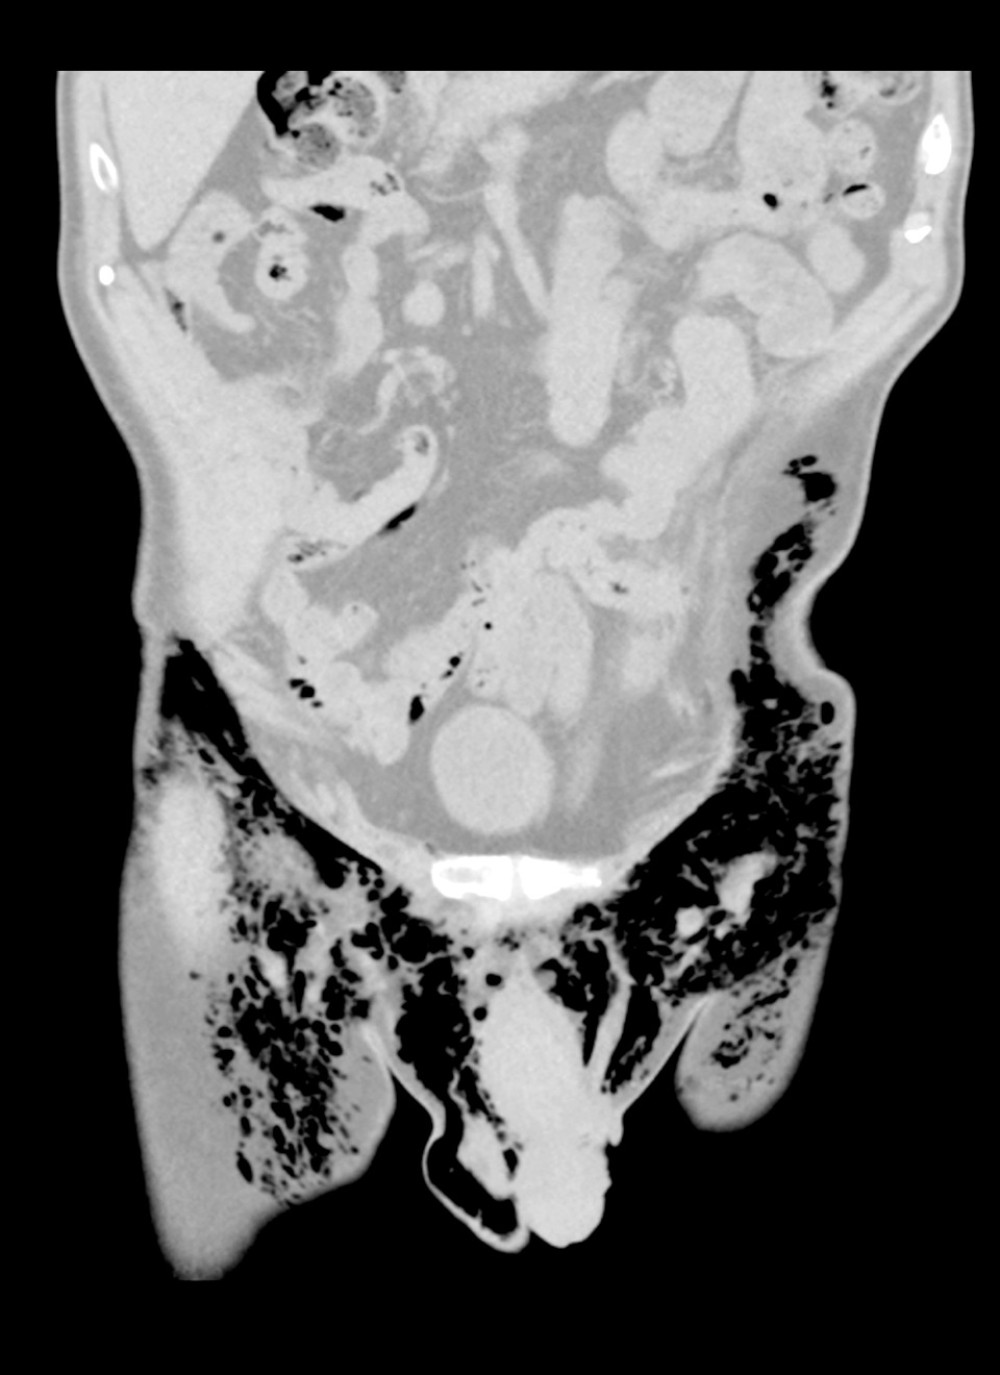

In the emergency department, he was afebrile (37°C), with a heart rate of 80 beats per minute, blood pressure 104/70 mmHg, respiratory rate of 36 breaths per minute with SpO2 of 100% while breathing 2 L/min of oxygen via nasal cannula. He was alert and oriented in mild distress. A physical exam revealed a marked crepitus from head to thigh with bilateral orbital emphysema making it difficult to visualize his left pupil. He had a regular rate and rhythm on cardiac auscultation. Palpable crepitus was appreciated throughout the anterior chest, but without Hamman’s sign or an accessory crunching sound. Respirations were non-labored with decreased breath sounds bilaterally. His scrotum was tender to palpation with a dehis-cent left scrotal wound. The scrotum was not grossly swollen and had no signs of free air or rapid expansion. Routine laboratory results were unremarkable except for mild leukocytosis of 12.2 k/mm3 (Table 1). A chest X-ray disclosed bilateral pneumothoraces, pneumomediastinum, and excessive sub-cutaneous air. Two chest tubes were placed before obtaining computed tomography (CT) of the chest, abdomen, and pelvis. Being in a small local emergency department, he was transferred to a larger regional hospital for further treatment. Upon arrival, concern for worsening of the right-sided pneumothorax prompted a repeat CT chest, abdomen, and pelvis (Figures 1–3). This study revealed that the chest tube was not communicating with the pneumothorax, which had increased in size from the previous report. He had placement of an additional chest tube. On hospital day 3, with resolution of the pneumotho-races, his chest tubes were removed and he was discharged in stable condition.

The pneumoscrotum and associated subcutaneous emphysema of the perineum and thighs took an abnormally long time to resolve. The patient required additional scrotal procedures and eventually needed bilateral orchiectomy. After nearly 2 years, all the subcutaneous emphysema of the perineum and thighs resolved, as noted in the most recent CT scan.